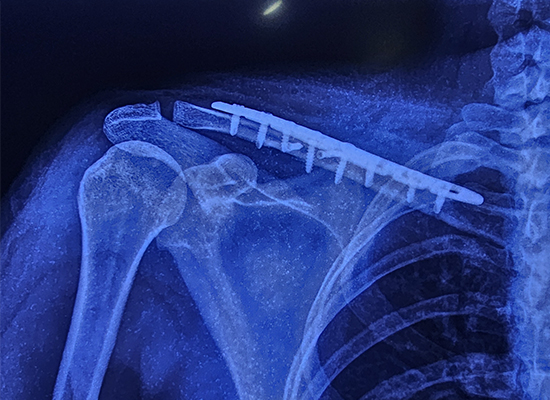

The surgery involved using a specialized S-clavicle locking plate, an advanced implant designed to provide stability in multi-fragmented fractures. The 8-hole plate was chosen due to its precise fitting and ability to support the fracture during the healing process. The operation went smoothly, and no complications arose during the procedure.

Implant Type : S-clavicle locking plate

Size : 8-hole, right side

Material : Titanium alloy for strength and durability

Usage : Designed for stabilizing clavicle fractures